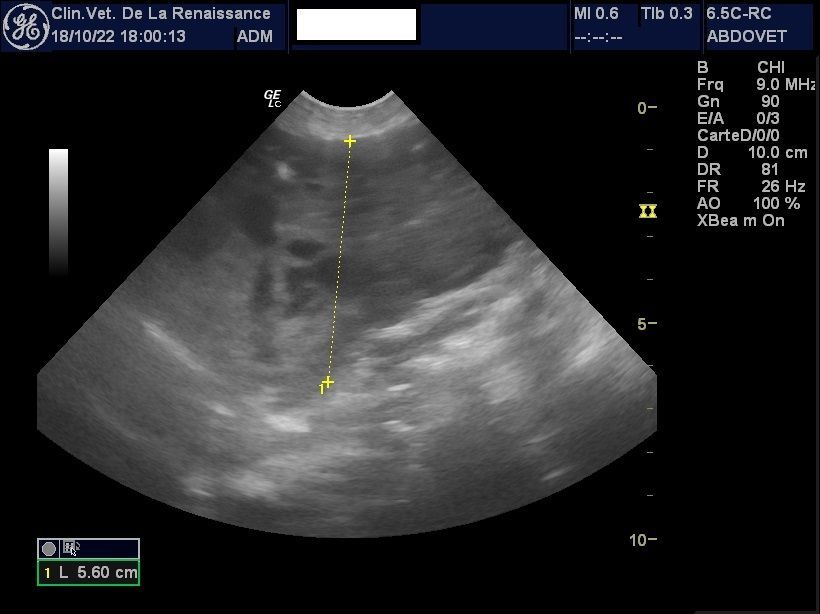

L'échographie

La clinique est équipée d'un échographe pour l'exploration de la cavité abdominale et de ses organes. Nous pouvons réaliser une échographie ciblée sur un organe ou sur l'ensemble des organes abdominaux, dans le cadre d'un diagnostic ou le suivi d'une pathologie ou d'une gestation. Un doppler permet dans le cadre de la gestation de mesurer la fréquence cardiaque des chiots. L'échographie peut être réalisée avec ou sans anesthésie générale en fonction de l'animal.